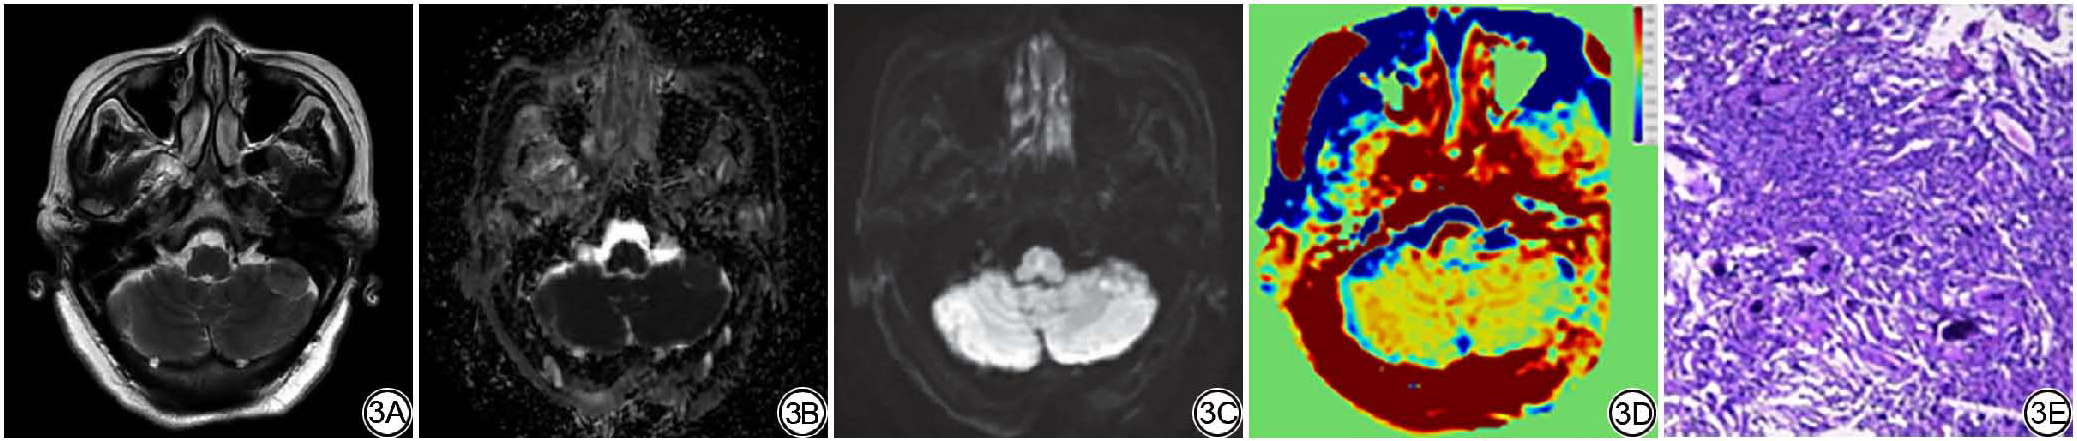

MUSE-DWI及APT的图像后处理分别在GE-ADW(4.7,GE Healthcare)与GE iQuant(2.0,GE Healthcare)工作站上完成,以获取ADC图及APT后处理图像。随后,所有图像均通过MATLAB(MathWorks,美国)平台下的SPM工具包统一配准至T2 FLAIR序列。最后由两位分别拥有5年与10年神经影像诊断经验的住院医师及主治医师,采用双盲法,参照T2 FLAIR及增强T1WI(T1WI+C)图像手动勾画感兴趣区(region of interest, ROI),过程中注意避开肉眼可见的囊变、坏死、出血及磁敏感伪影显著区域,选择强化程度明显的实性区域,避开肉眼可见的粗大血管及血管流空影,勾画3个大小一致的ROI(面积约0.25~0.35 cm2)。(1)平均ADC值测量:扫描后将DICOM数据传输至GE ADW 4.7工作站,MUSE-DWI衍生成的ADC图,按照上述原则放置ROI,测量平均ADC值,测量3次,计算平均值。(2)APTw图像参数测量:采用MRI主机系统自带软件获取APT定量图进行测量,按照上述原则放置ROI,测量APT信号值,测量3次,计算平均值(图1)。

图1  ROI示意图。1A:T2 FLAIR;1B:T1WI+C;1C~1D:MUSE-DWI及衍生ADC图;1E:APT。参考结合T2 FLAIR及T1WI+C肿瘤实质高信号区域(箭)勾画ROI,避开囊变、坏死区域。ROI:感兴趣区;FLAIR:液体衰减反转恢复;T1WI+C:增强T1WI;MUSE-DWI:多重灵敏度编码扩散加权成像;ADC:表观扩散系数;APT:酰胺质子转移。

Fig. 1  Schematic diagram of the ROI. 1A: T2 FLAIR; 1B: T1-weighted imaging with contrast (T1WI+C); 1C to 1D: MUSE-DWI and the derived ADC map; 1E: APT. The ROIs are delineated with reference to the hyperintense regions in the tumor parenchyma (arrows) as seen on T2 FLAIR and T1WI+C, while avoiding cystic and necrotic areas. ROI: region of interest; FLAIR: fluid attenuated inversion recovery; T1WI+C: contrast enhanced T1-weighted imaging; MUSE-DWI: multiplexed sensitivity encoding diffusion weighted imaging; ADC: apparent diffusion coefficient; APT: amide proton transfer.